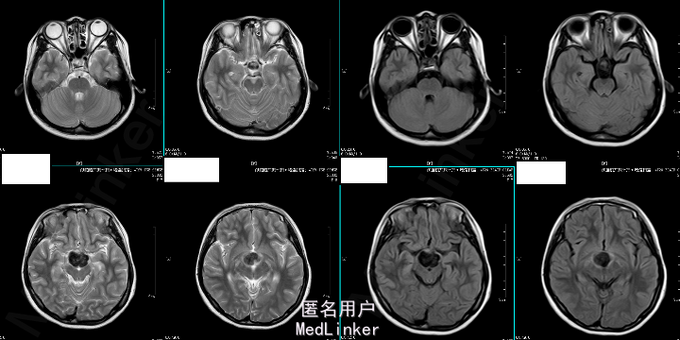

诊断:鞍上区恶性肿瘤:颅内生殖细胞肿瘤 处理:放疗。(3D-CRT 36GY/FX),胸腺肽增强免疫力及副作用对症处理。 (2015-06-24复查头颅MR结果如下)